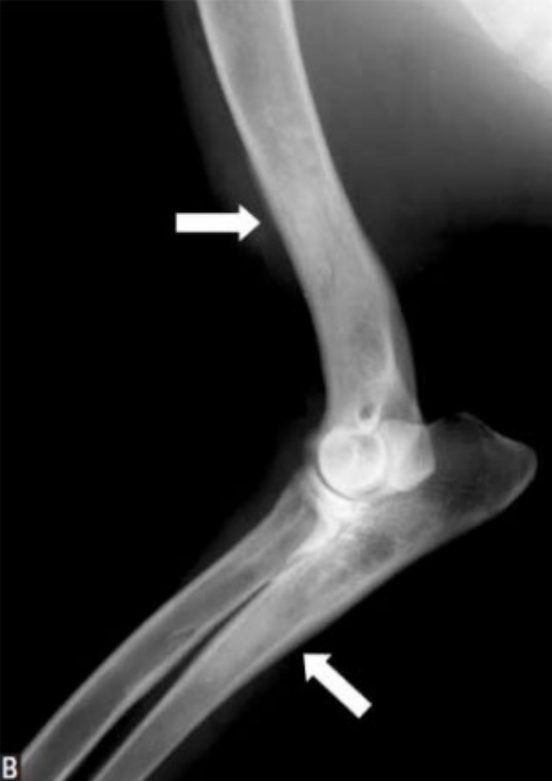

- 범골염 증상 (비교적 명확)

- 범골염 증상

- 범골염

- trabecular pattern

- 겉질과 골수관의 대비가 감소. 구별이 잘 되지 않아 경계가 흐릿